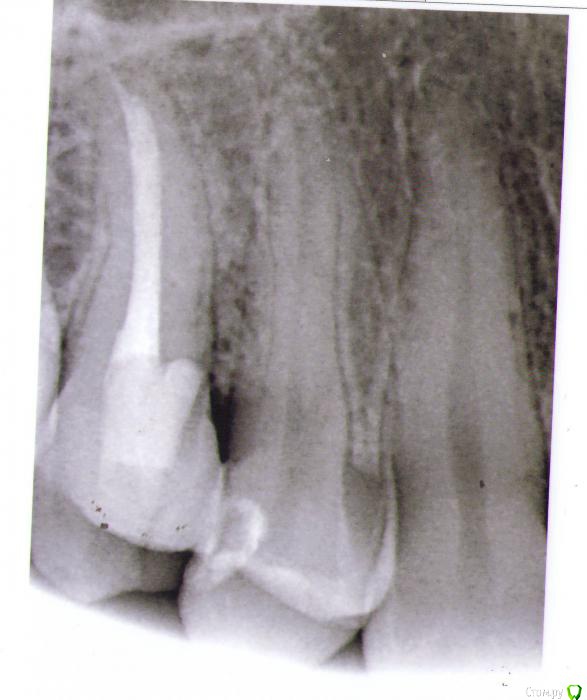

Zub15 Опубликовано 14 мая, 2015 Поделиться Опубликовано 14 мая, 2015 Здравствуйте! Зуб1.5 лечили по глубокому кариесу осенью 2014г. После этого около 3 месяцев не проходили самопроизвольные ноющие боли. В итоге в конце января 2015г. постановили что пульпит таки необратимый и провели эндодонтическое лечение. Через 2 недели появилась боль от горячего. Пока попала к доктору прошло дней 5. За это время ощущения от просто чувства тяжести в первые дни усилились до очень острой, нарастающей первые несколько секунд боли, по продолжительности около 10 минут и в эти моменты причинный зуб реагировал еще и на накусывание. В середине февраля зуб снова вскрыли, искали дополнительные каналы - не нашли, обработалди еще раз тот же канал и оставили кальций под временной пломбой. Первые несколько часов после лечения все было хорошо, зуб не болел. К вечеру появилась ноющая боль, которая постепенно училивалась и к ночи стала нестерпимой. К утру следующего дня боль не прошла, зуб снова вскрыли, заменили кальций и снова под временную пломбу. После все вроде нормализовалось. Через 2 недели когда убрали кальций и запломбировали каналы постоянным материалом снова такая же картина. Первые несколько часов все норм, к ночи разболелся сильно. 4-5 дней эту боль перетерпела и потом постепенно она пошла на спад. В итоге еще недели 2 зуб наблюдали под временной пломбой, боли как таковой не было, но реагировал на постукивание. На сегодняшний день сильной боли нет, на горячее тоже не реагирует, но периодически слабо поднывает где-то в районе 1.4-1.5 чаще по ночам и если в это время пошатать зуб 1,5 - начинает ныть сильнее. Если постучать больно только когда стучишь по передней стенке. И больно чистить нитью между 1.4 и 1.5, причем больно не десну а боль где-то в районе контактного пункта, чуть только вводишь нить сразу больно. На первом снимке фрамент ОПТГ зуб после лечения глубокого кариеса, до лечения каналовВторой снимок в процессе перелечивания когда заболел от горячего, корневая пломба постоянная, коронковая пломба временная.Третий снимок - на сегодняшний день. Спасибо. 1- http://s013.radikal.ru/i322/1505/c2/0fc23f57af58.jpg2- http://s019.radikal.ru/i622/1505/ca/cf134a067f86.jpg3- http://s019.radikal.ru/i637/1505/2c/da877627c607.jpg Ссылка на комментарий

Scrabble Опубликовано 14 мая, 2015 Поделиться Опубликовано 14 мая, 2015 (изменено) Эндо нормально, а между 14 и 15 проблемы с пародонтальным прикреплением(либо кариес корня был, либо немного не в том направлении бором пошли) Сделайте лучше либо керамическую вкладку, либо ВКВ и коронку. Заодно дистальную поверхность 14 посмотрит врач-может, там уже кариес успел образоваться. Изменено 14 мая, 2015 пользователем Scrabble Ссылка на комментарий

Гарриевич Опубликовано 15 мая, 2015 Поделиться Опубликовано 15 мая, 2015 Скорее всего проблема в связочном аппарате, то, что Вы описываете характерно. По помледним снимкам может это и перфорация, а может просто наложение. Снимки все таки двухмерные, а зубы у нас обьемные Ссылка на комментарий